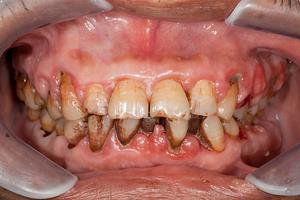

Diş eti kanaması; zararlı mikroorganizmaların ağız içerisindeki etkinliklerinin ve beraberinde oluşan enfeksiyonların sonucudur. Önemli bir diş eti hastalığı belirtisidir. Diş eti kanaması genellikle kendisini diş fırçalama işleminden sonra belli eder. Ağrının sızının henüz gerçekleşmediği, sadece kanamanın görüldüğü bu evre; diş eti hastalıklarının en erken evresidir.

Diş eti kanaması bir hastalık değil, bir hastalık belirtisidir. Diş etinin çeşitli sebeplerle iltihaplanması sonucunda diş eti kanaması oluşur. Bundan dolayı diş eti iltihabının sebepleri; diş eti kanamasının da sebepleri olacaktır. Diş eti iltihabı, diş eti kanaması ve diş eti çekilmesi birbirini takip eden durumlardır. Bütün bu durumların altında yatan en önemli sebep ise ağız bakımının ihmal edilmesidir.

Diş taşı oluşumları; diş eti hastalıklarının en büyük sebebidir. Diş taşı; uzun süre dişten temizlenmemiş yapışkan ve renksiz bakteri plaklarının, tükürük salgısındaki minerallerle birleşerek kireç halini alması durumudur. (Kalsifikasyon: Kireçleşme/kemikleşme) Diş taşı aynı zamanda tartar ve kalkülüs isimleriyle de anılır. Bunlar dişe sıkıca tutunan yapılardır. Yüzeyleri oldukça kötüdür ve geçirgendir. üzerindeki bakterilerle birlikte enfeksiyon oluşturarak diş etinin iltihaplanmasına ve diş eti kanaması sorununun oluşmasına sebep olur. Diş taşı dışında diş eti kanamasına sebep olan bazı önemli etkenler şunlardır:

Diş eti kanaması; diş eti iltihabının belirtilerinden birisidir. Bu sebeple diş eti iltihabı belirtileri aynı zamanda diş eti kanamasının belirtileri hükmünde olacaktır. Diş eti iltihabının başlangıç aşamasına “gingivitis” denilmektedir. Gingivitis aşamasında; kızarıklık, şişlik ve en ufak bir dokunuş ya da diş fırçası müdahalesinde diş eti kanaması görülür. Eğer bu önemli belirtiler dikkate alınır ve ağız bakımına eskisinden çok daha fazla itina gösterilirse, bu durumdan kurtulmak ve ağız içini eski sağlığına kavuşturmak mümkün olacaktır. Belirtiler dikkate alınmaz ve dişlerdeki bakteri plaklarının diş taşı haline gelmesine izin verilirse, iltihap hızla ilerleyecek ve doktor müdahalesine ihtiyaç olacaktır.

İltihaplı dokular ve diş etlerinin iç kısmında biriken bakteriler, geçmek bilmeyen ağız kokularına sebep olmaktadır. Bakteri plaklarından fırçalayarak kurtulabilmek mümkündür; ancak “diş taşları” fırçalayarak gidecek oluşumlar değildir. Profesyonel müdahale gerekir.